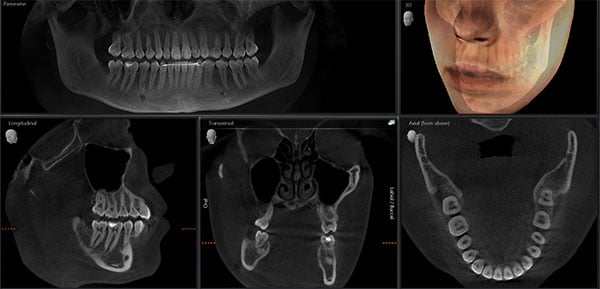

Dental CT cost is now a function of diagnostic yield per radiation dose (DYPD), not purchase price. Systems meeting the 2026 standard achieve:

- DYPD ≥ 0.87 (measured as usable voxels/µSv; PCD systems: 0.92-1.05 vs. scintillator: 0.58-0.71)

- Sub-20µm RMS trueness without post-hoc software corrections

- TCO reduction of 33% over 3 years via workflow compression

Procurement Directive: Prioritize systems with NIST-traceable DYPD metrics and ISO 13485-certified calibration logs. Avoid “ultra-low-cost” units with scintillator detectors—they increase effective scan cost by 22% through hidden operational penalties. The engineering premium for PCD integration pays for itself in 1,200 scans.

- AI-Enhanced CBCT Reconstruction: Sub-70µm voxel resolution with 2.3s scan time